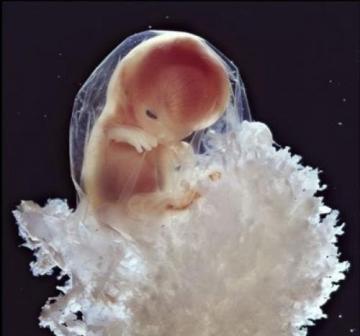

ну а если в цвете, то нашла вот такую картиночку